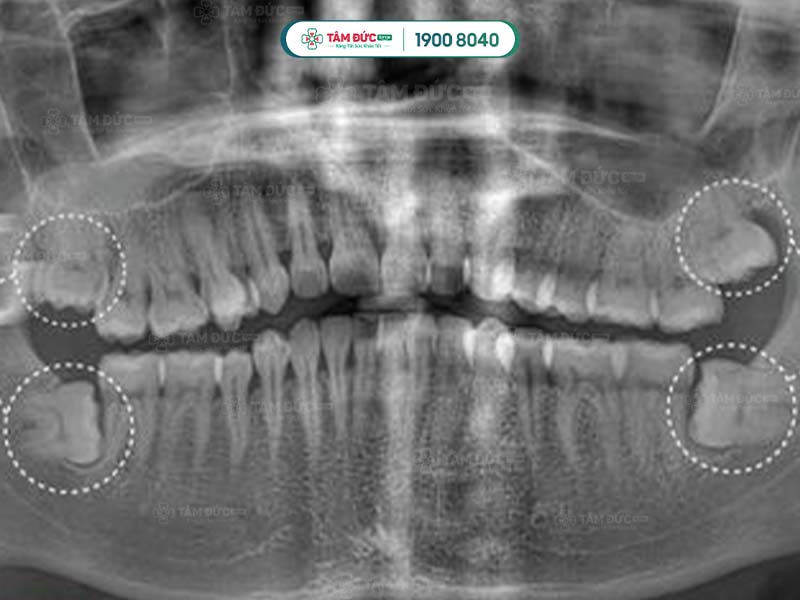

Răng khôn thường mọc ở phía sâu trong khoang miệng, sau răng hàm thứ 2. Răng khôn thường mọc ở 4 vị trí góc miệng: hàm trên trái, hàm trên phải, hàm dưới trái và hàm dưới phải.

Một số ít trường hợp, răng khôn không mọc ở cả 4 vị trí. Có người chỉ mọc 2 chiếc, có người chỉ mọc 1 chiếc. Quý khách không thể tự đếm hay nhìn thấy răng khôn mọc ngầm bằng mắt thường, mà cần phải thông qua chụp phim X-Quang.

Chân của răng khôn có thể xòe nhiều hướng với nhiều hình thái khác nhau. Ngoài ra, việc răng khôn mọc ngầm cũng tiềm ẩn nhiều nguy hiểm. Nếu để thời gian lâu dài, chân răng khôn mọc ngầm hoặc lệch có thể ảnh hưởng đến các dây thần kinh xung quanh.

Vì vậy, trước khi tiến hành phẫu thuật răng khôn, bác sĩ sẽ xác định răng khôn có mấy chân. Việc này giúp phòng tránh những sai sót trong khi phẫu thuật.

Đầu tiên là bước thăm khám lâm sàng để thu thập những chỉ số cần thiết như: chỉ số đông máu, số lượng tiểu cầu… Tiếp đến, Quý khách sẽ được chụp X-quang nhằm xác định răng khôn có mấy chân và hình dáng của chân răng khôn.

Sau khi nhận kết quả chụp phim, bác sĩ tiến hành đánh giá tình trạng và độ khó của phẫu thuật. Tiếp đến, Quý khách sẽ được tiêm thuốc gây tê tại chỗ. Với trường hợp răng khôn dễ nhổ: bác sĩ tiến hành rạch trên nướu, làm sạch vùng phẫu thuật để tiếp cận và nhổ bỏ răng khôn. Trường hợp khó hơn: răng khôn có nhiều chân thì cuộc phẫu thuật có thể kéo dài. Lúc này bác sĩ sẽ rạch và cắt từng chân của răng khôn để đảm bảo an toàn.